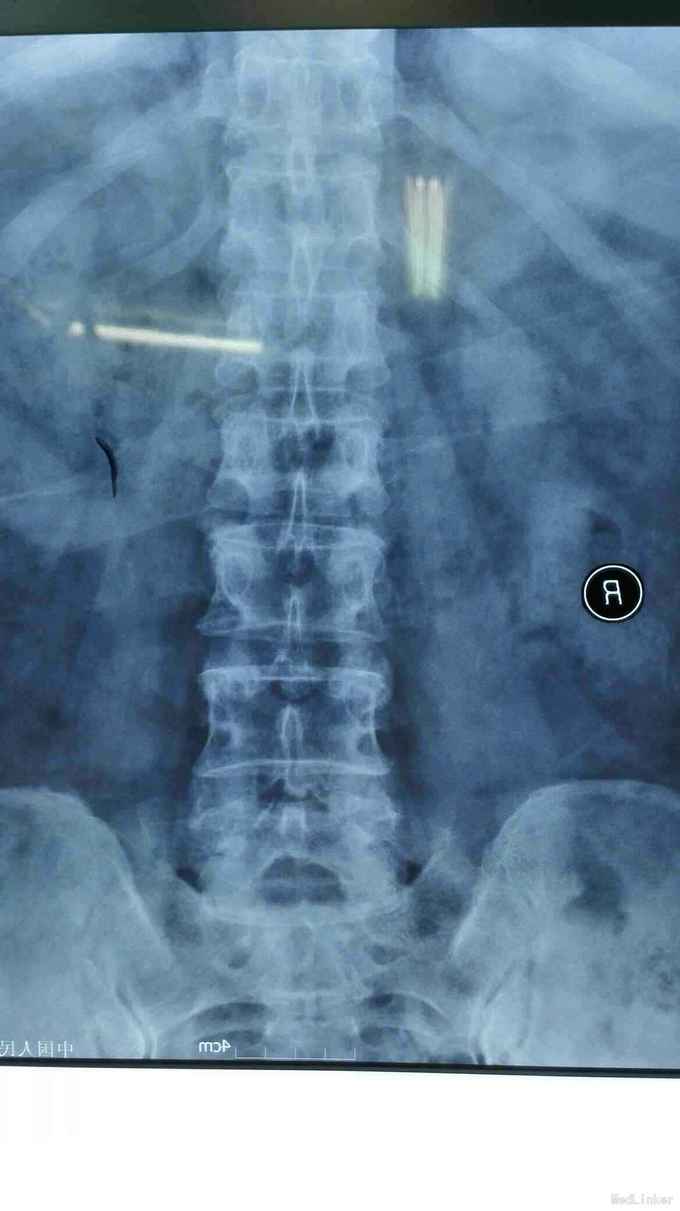

查体符合腰5神经根受压体征。腰椎CT、MRI提示腰4/5椎间盘突出,椎管狭窄。

考虑腰椎间盘突出伴椎管狭窄症。行椎间孔镜下髓核摘除,椎间孔成形。